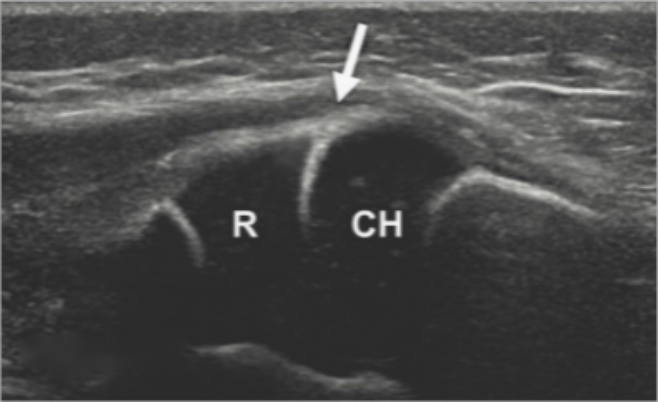

超声在儿童肘部损伤诊断中的作用已被多篇文献所证实,但目前尚无全面、规范的方法用于临床实践。在使用超声对孟氏骨折桡骨头脱位的病例中,评估肱桡关节是否有环状韧带卡入时,我们通常在肱桡关节前矢状位纵切面观察桡骨头相对于肱骨小头的位置变化,并在此测量肱桡间距;在肱桡关节前矢状位纵切面观察旋后肌与桡骨头的位置关系;在肱桡关节前矢状位纵切面观察环状韧带是否存在嵌顿[7]。当出现以下异常超声声像时,通常认为存在环状韧带卡压:(1) 环状韧带线性高回声图像消失(见图1(a)长箭头处);(2) 环状韧带和(或)旋后肌被卡压在肱桡关节内,呈现“J”型的低回声图像(见图1(b)小箭头处) [8];(3) 肱桡关节内,肱骨小头与桡骨之间的肱桡间距,与对侧相比增宽。

(a) (b)

Figure 1. Abnormal sonographic appearance of the anterior sagittal longitudinal planea

1. 前矢状位纵切面异常超声表现